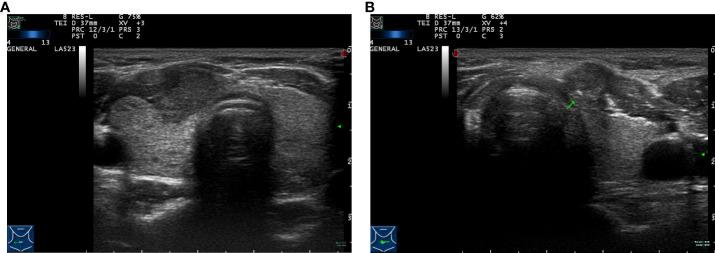

Clinical and ultrasonic risk factors for high-volume central lymph node metastasis in cN0 papillary thyroid microcarcinoma: A retrospective study and meta-analysis.

cN0 期甲状腺微小乳头状癌高容量中央区淋巴结转移的临床及超声危险因素:一项回顾性研究与Meta分析

Clin Endocrinol (Oxf). 2023 Apr;98(4):609-621. doi: 10.1111/cen.14834. Epub 2022 Nov 3.